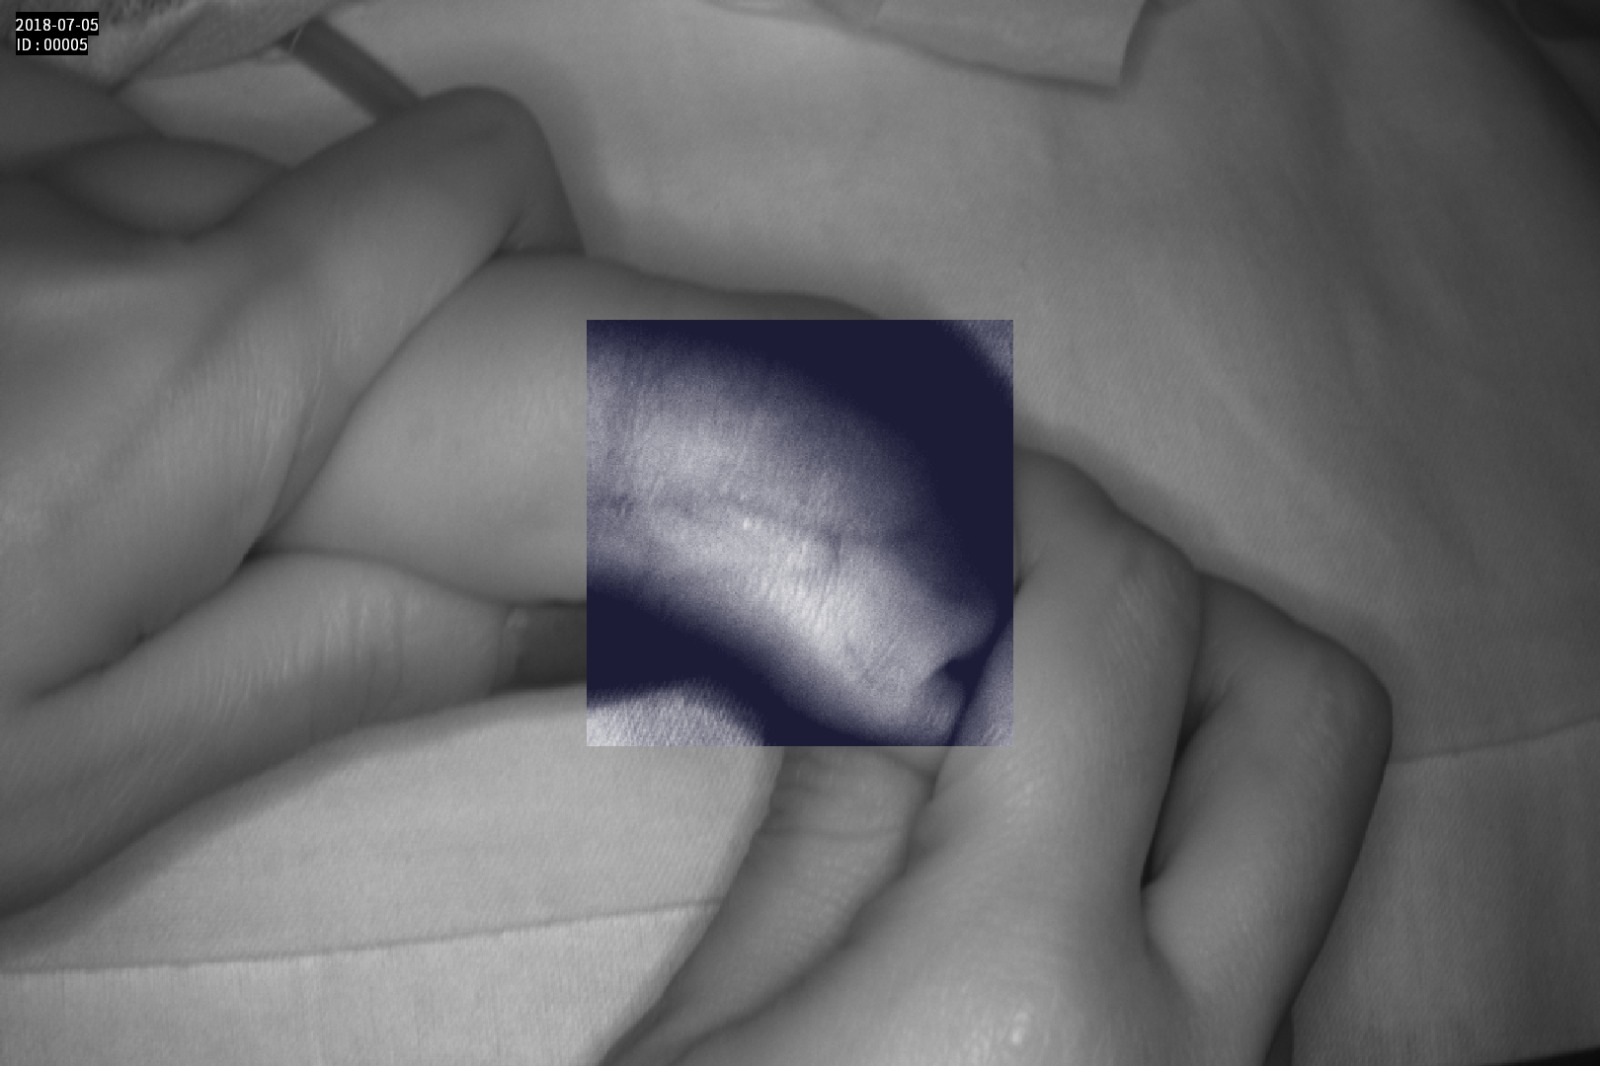

Dispozitiv medical portabil, non-contact, ce ajută la vizualizarea venelor pentru efectuarea puncției venoase, intervențiilor chirurgicale plastice, diagnosticul venelor varicoase.

Grad mare de detecție a venelor greu vizibile până la 10 mm adâncime (inclusiv vene faciale)

Imaginea venelor este proiectată pe monitorul propriu în timp real si ajută la identificarea corectă și precisă

Multiple aplicații de vizualizare vene atât la sugari cât și la pacienții obezi sau în urgențe indiferent de tonul de culoare a pielii